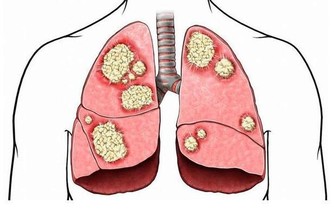

中醫提及,有心血管疾病的患者,多半有不明原因的頸部酸痛、喉嚨痛、胸痛、胃痛,甚至小指內側、靠近無名指的整條手少陰心經會麻、有緊縮感,所以問診時就會特別留意。